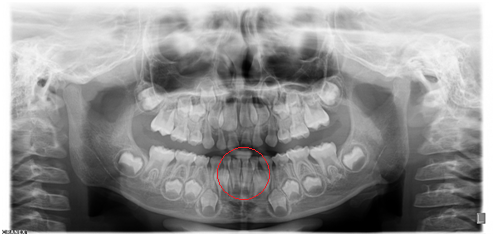

【全景牙片】

◆乳牙的萌出和替换

◆多生牙

◆阻生智齿

◆牙周炎引起的牙槽骨吸收